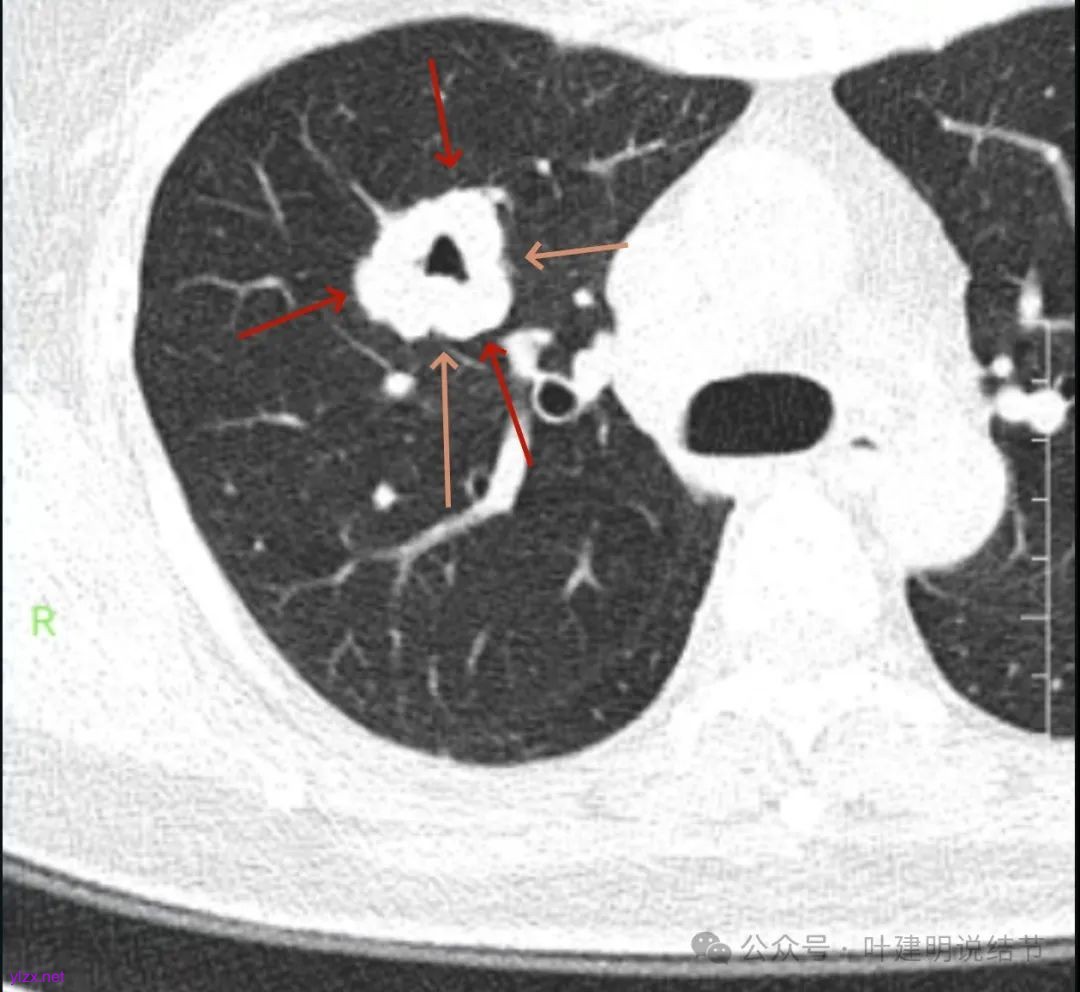

咳嗽近三周,CT检查提示右肺上叶空洞病变。

影像展示与分析:

腔静脉旁明显肿大淋巴结。

你的右上叶这个病灶基本上肯定是肺癌,要尽快处理。从影像上看有以下特点:1、整体轮廓清楚,不似普通炎症的周围有晕或阻塞性改变;2、边缘明显的浅分叶,总体上的感觉膨胀性明显,不管哪个层面看上去都是鼓鼓的;3、边缘区域有磨玻璃成分而且也是分叶状的;4、部分层面见血管进入;5、空腔病灶的壁厚薄不均,内壁不光滑。我考虑中低分化肺癌,由于腔静脉旁有明显肿大淋巴结,需要进一步完善增强CT以及PET-CT检查以明确有无远处转移,是否仍可手术治疗(从病灶本身来说是可以肺叶切除治疗的)。要尽快处理。意见供参考!